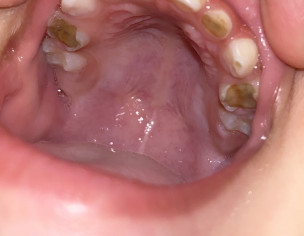

Any peads dentist here? My 2 and a half year old daughter’s upper teeth and molars look like this. Her baby teeth came out like this so I doubt its cavity, her jaudice was not high, it was mild when she was born. Also she began teething very early, like around 3.5 months. She sometimes complain of pain while chewing anything hard.

Well she is just 2.5 yrs old so I don’t recommend you to get her teeth extracted right at this age so that permanent teeth don’t erupt malaligned.Maintain her good oral hygiene along with visit to a dentist for her root cleaning and filling of her teeth. Jaundice has no such link with this condition. Please make sure her brushing is good. After milk make her rinse her mouth atleast. If she feels pain of any kind then go for syrup Panadol OR Syrup Brufen (1+0+1)teaspoons

you need to restore those teeth, its so early for them to shed

stop sugar intake, make sure to brush her teeth yourself, visit dentist for proper evaluation and treatment.

Ths is not because of juandice she had. Avoid any sticky food like choclate toffees these things will cause caries progression she has. Use normal saline rinses. Add salt in Lukewarm water and do rinses after every meal. Especially before going to bed. Ths is precautionary measure. Further she needs a complete check up with x ray. Thank you